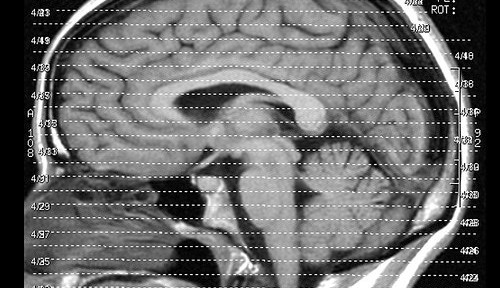

この研究は2ヶ月間にわたって、23人の若年成人に「スーパーマリオ64」を毎日30分ずつプレイさせ、MRI(磁気共鳴画像)で脳を測定。ゲームをしなかったグループと比較する方法で行われた。

結果、ゲームをした被験者は、空間進行や戦略計画を司る3つの領域(右海馬、右前頭前皮質、小脳)において、記憶力のよさと関連する「灰白質」が増大したという。